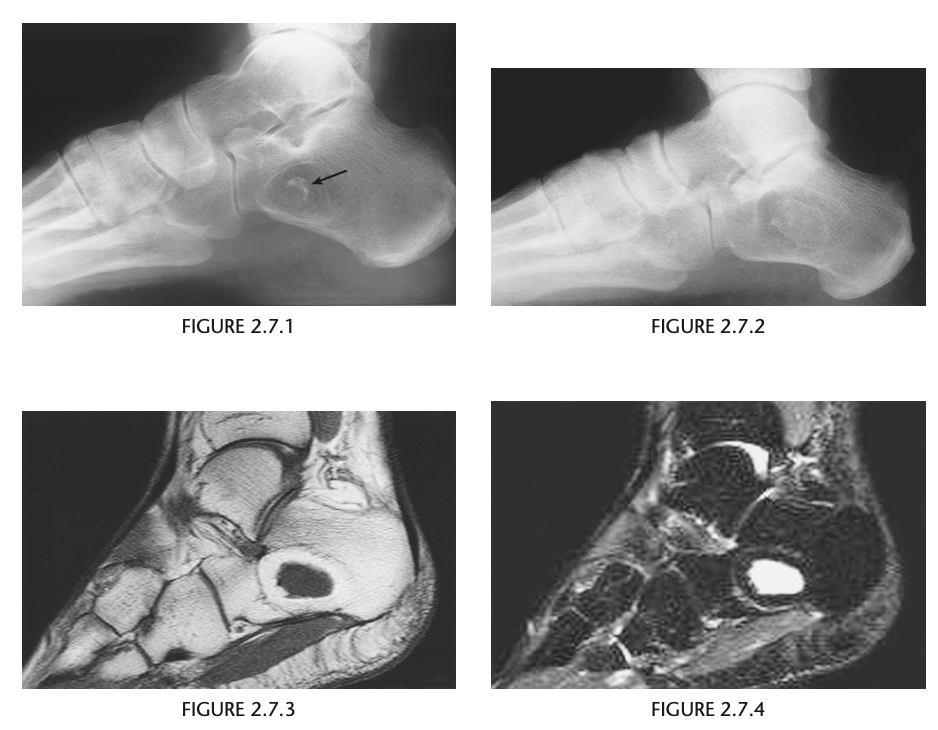

Foot pain

A lateral radiograph of the left foot demonstrates a prominent talar beak

­ (arrow) and bony sclerosis overlying the middle

facet (arrowheads). Coronal CT through the middle

facet shows talocalcaneal fusion, with bony bridging between the talus and the sustentaculum tali of the

calcaneus

Diagnosis: Tarsal coalition

abnormal fusion

of one or more of the tarsal bones, may be fibrous,

cartilaginous, or osseous and may be posttraumatic, or congenital.

Most

common tarsal coalitions are calcaneonavicular and

talocalcaneal.

Radiographically, calcaneonavicular coalition may

be suspected because of elongation of the anterior

facet of the calcaneus on radiographs (i.e., anteater

sign. CT can also be used to confirm coalition and shows

­ sclerosis at the articulation

Congenital coalition usually evolves from fibrous to osseous

coalition and may not be apparent on the initial

evaluation

Talocalcaneal coalition can result in dorsal beaking

of the talar head (Fig. 2.3.6, arrowhead), the so-called

C-sign (arrows)